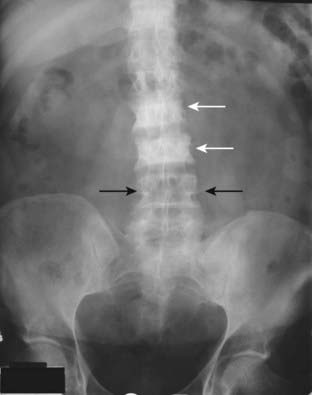

Figure 21-7 Focal increase in bone density from carcinoma of the breast.

A frontal view of the lumbar spine and pelvis demonstrates abnormally dense vertebral bodies most marked at L2 and L3 (solid white arrows). Notice how the pedicles are obscured by the abnormally increased density of the vertebral body compared to the normal pedicles at L4 (solid black arrows). Dense, white vertebrae are called ivory vertebrae. Osteoblastic metastases from carcinoma of the breast and prostate are two causes of an ivory vertebra.